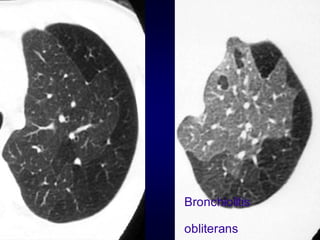

• 123.

Pathology in blackareas Airtrapping: Airway Disease Bronchiolitis obliterans (constrictive bronchiolitis) idiopathic, connective tissue diseases, drug reaction, after transplantation, after infection Hypersensitivity pneumonitis granulomatous inflammation of bronchiolar wall Sarcoidosis granulomatous inflammation of bronchiolar wall Asthma / Bronchiectasis / Airway diseases

• 124.

Airway Disease what yousee…… In inspiration sharply demarcated areas of seemingly increased density (normal) and decreased density demarcation by interlobular septa In expiration ‘black’ areas remain in volume and density ‘white’ areas decrease in volume and increase in density INCREASE IN CONTRAST DIFFERENCES AIRTRAPPING

Hypersensitivity pneumonitis Extr. Allerg.Alveolitis (EAA) HRCT Morphology acute - subacute acinar (centrilobular) unsharp densities ground glass (patchy - diffuse) chronic: fibrosis Intra- / interlobular septal thickening Irregular interfaces Traction bronchiectasis